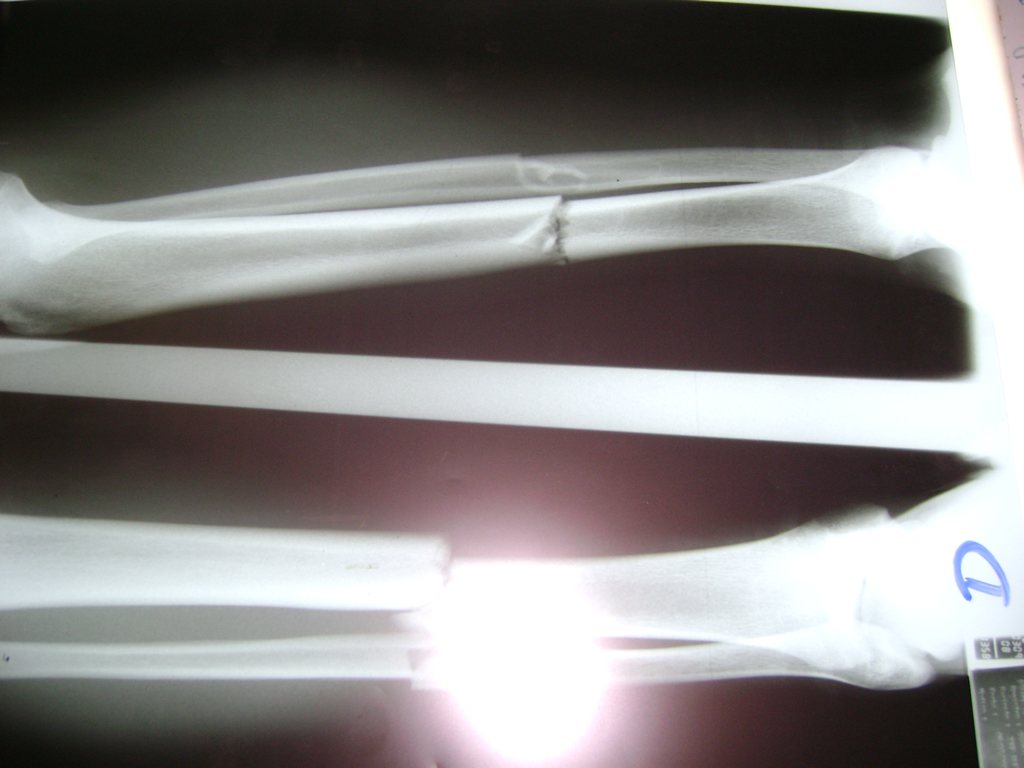

Aunque cada uno de estos huesos puede fracturarse por separado, normalmente la rotura es una lesión que se produce de forma conjunta

Debido a la fina cobertura de piel que recubre la tibia y el peroné, las fracturas generalmente son abiertas, es decir, el hueso roto rasga la piel, atravesándola. Las fracturas de tibia y peroné generalmente se producen por un fuerte impacto o torsión.